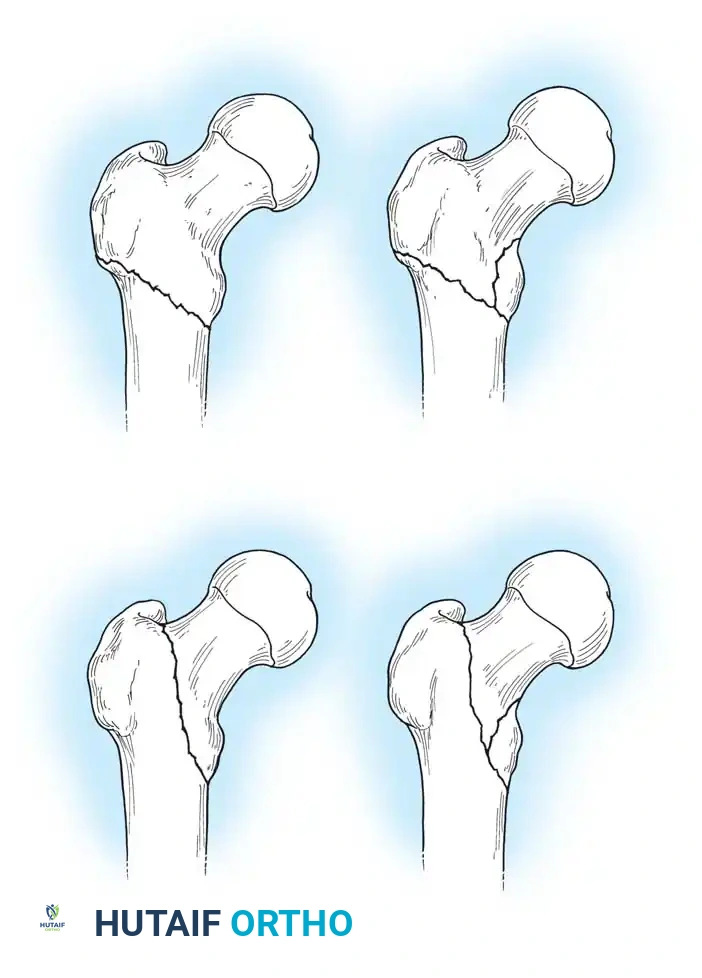

The Evans classification divides fractures into stable and unstable patterns based on the integrity of the posteromedial cortex (the calcar femorale).

* Stable: The posteromedial cortex is intact or can be anatomically reduced.

* Unstable: Characterized by posteromedial comminution, subtrochanteric extension, or a reverse obliquity pattern (where the fracture line extends outward and downward from the lesser trochanter). Reverse obliquity fractures are highly unstable due to the medializing pull of the adductor musculature.

- 31-A1: Simple, two-part fractures (Stable).

- 31-A2: Comminuted fractures with posteromedial fragmentation (Unstable).

- 31-A3: Reverse obliquity or transverse fractures extending into the lateral cortex (Highly Unstable).